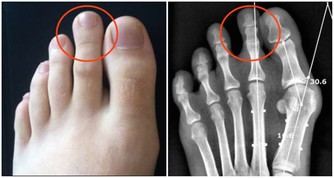

攝入過多蛋白質——高尿酸血症:蛋白質吃的過多,會導致體內的血尿酸濃度升高,引發高尿酸血症。血尿酸濃度升高對腎臟的毒作用非常大,容易發展成慢性腎功能衰竭即尿毒症。